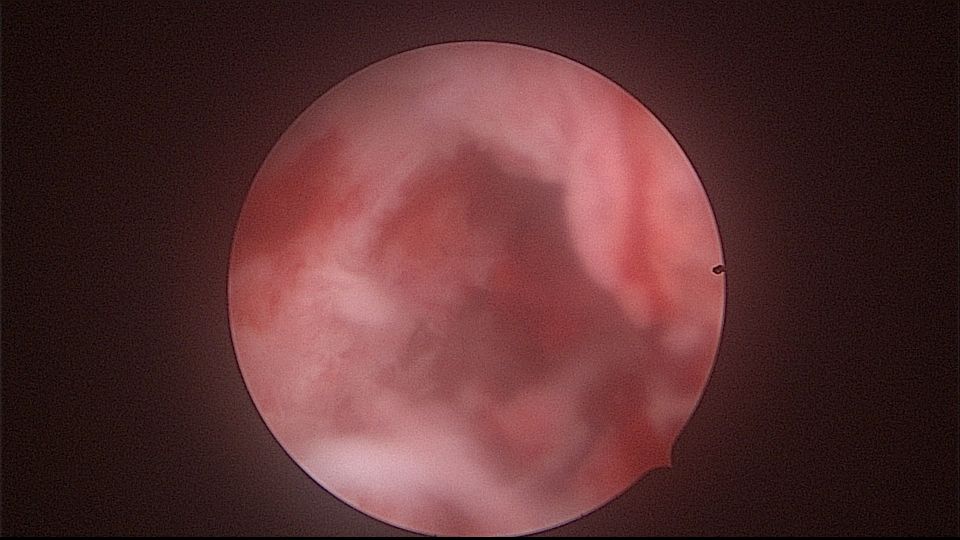

患者52岁,G2P1,顺产1次。安环27年,外院取环失败。病人肥胖,B超提示子宫前位,节育环距宫底0.9cm。子宫极度前倾前屈位,宫腔镜见宫颈管组织杂乱,宫颈管上段右前壁见假道,膨宫不良,视野模糊,寻找宫腔方向困难,准备B超监护过程中,拆走扩阴器,腹部下压子宫,终于寻找到了宫颈内口,看到了爱母环下端,异物钳牵拉出节育环,再次探查宫腔,无其他异常。